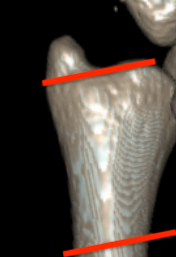

Classification ulna styloid fractures

| Type 1: Tip | Type 2: Base | Type 3: Proximal to styloid |